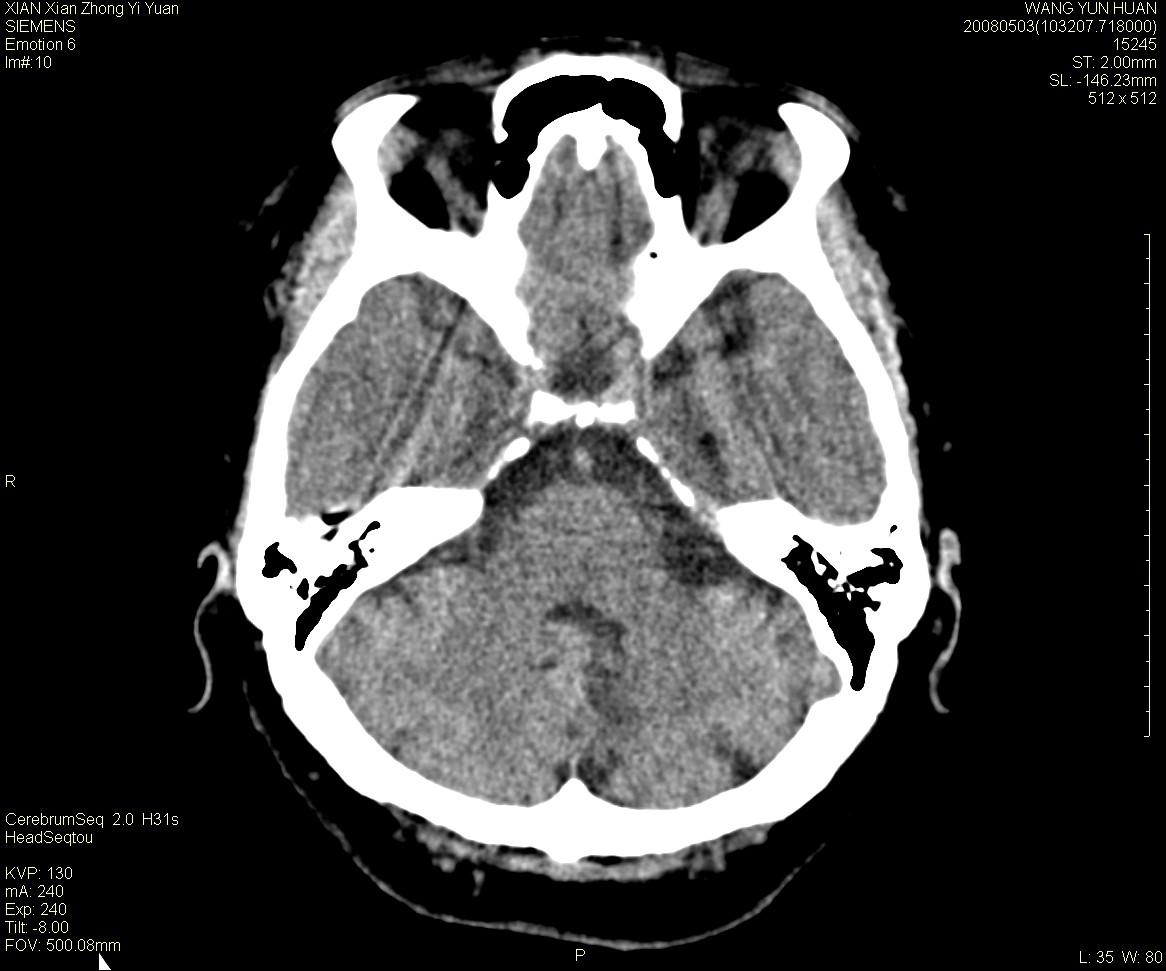

标题: CT13219:(补充强化)请会诊,患者女,60岁,头晕,大家看 [打印本页]

标题: CT13219:(补充强化)请会诊,患者女,60岁,头晕,大家看

病灶显示轻度强化,ct增加4hu左右,大家看是什么肿瘤.

小脑蚓部占位,考虑脑膜瘤。增强吧

小脑蚓部囊型肿块,内有实性结节及钙化点。增强后囊壁及结节轻度强化。

考虑蚓部星形细胞瘤(ⅱ级可能性大)。

小脑蚓部肿块,周围无明显占位效应及水肿带,增强轻度强化,考虑低分级星形细胞瘤。